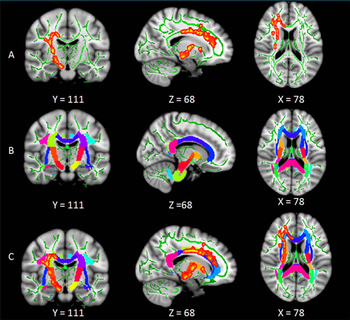

Each participant also underwent brain MRI with a specialized technique called diffusion tensor imaging (DTI). DTI allows researchers to analyze the pattern of water movement along white matter tracts to identify a loss of tract integrity.

"We used a new method called Tract-Based Spatial Statistics that is highly sensitive to the microstructure of the white matter tract and provides multiple diffusion measures," Li said.

Results of the analysis showed that compared to the healthy controls, the insomnia patients had significantly reduced white matter integrity in several right-brain regions, and the thalamus which regulates consciousness, sleep and alertness.

"These impaired white matter tracts are mainly involved in the regulation of sleep and wakefulness, cognitive function and sensorimotor function," Li said.

In addition, abnormalities in the thalamus and body corpus callosum—the largest white matter structure in the brain—were associated with the duration of patients' insomnia and score on self-rating depression scale.